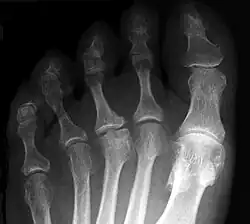

Morbus Köhler-Freiberg am 3. Mittelfußköpfchen

Der betroffene Vorfuß schmerzt bei Belastung, gelegentlich treten auch Schwellungen am Fußrücken im Bereich des Mittelfußköpfchens auf. Im Röntgenbild zeigen sich erst eine Veränderung in der Knochenstruktur des betroffenen Mittelfußköpfchens und erst später eine Abflachung und eine Verbreiterung (siehe Abbildung). Auf Dauer kann die Fehlform der Mittelfußköpfchens zu einer Arthrose führen.